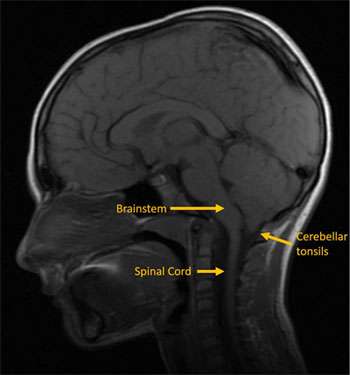

Chiari type 1 malformation is the most common type. It is the least severe and often diagnosed in late childhood or early adulthood. It is characterized by downward decent of the cerebellar tonsils into the foramen magnum (the opening at the base of the skull through which the brain connects to the spinal cord). This results in pressure and impaction of the brainstem, spinal cord and cerebellum and can interrupt normal flow of brain and spinal fluid through this region.